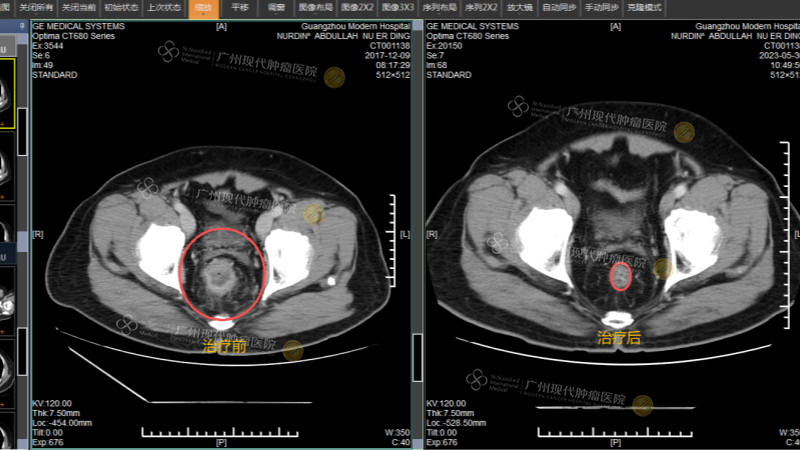

(治疗前CT片 vs 治疗后CT片)

在多次微创治疗后,他的肿瘤逐渐缩小,症状明显缓解,复查影像显示肿瘤已完全消失。

(努尔丁治疗前CT VS 治疗后CT)